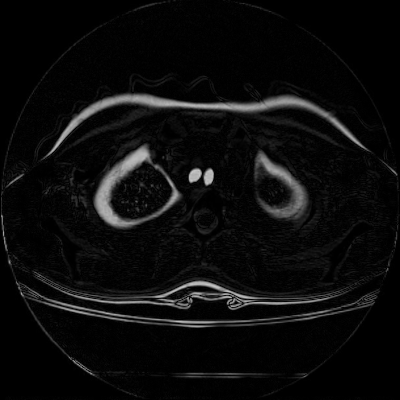

We then test our method on slices of chest CT images obtained from the Open Access Biomedical Image Search Engine [2]. Fig. 10(a) and 10(b) show the source image and target image respectively, and the intensity difference is shown in Fig. 10(c). The registration result obtained by our proposed method is shown in Fig. 10(d) (see also the result with the deformed underlying grid in Fig. 10(e)). From the final intensity difference plot in Fig. 10(f), it is easily to see that our method matches not only the two large components but also the small dot at the center very well. On the contrary, DDemons [47] produces a suboptimal registration result with a significantly larger mismatch of the small component at the center (see Fig. 10(g) and Fig. 10(h)).